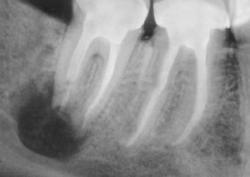

Зуб удаляют не только при сильной боли. Иногда пациент почти не предъявляет жалоб, но на рентгеновском снимке видно воспаление у корня, трещину, разрушение ниже десны или риск осложнений для соседних зубов. В таких ситуациях врач предлагает удаление как безопасный выход и заранее объясняет, какие варианты восстановления подойдут после заживления.

Метод выбирают по рентгеновскому снимку и осмотру. Врач учитывает форму корней, объем разрушения, состояние кости и мягких тканей. В практике применяются:

Без диагностики качественно удалить зуб сложно. В КДС перед вмешательством врач проводит осмотр, оценивает состояние десны, соседних зубов и прикуса. Далее выполняют рентгеновский снимок, чтобы увидеть корни, форму каналов, состояние кости и возможные воспалительные изменения.

Диагностика помогает выбрать тактику и снизить риск осложнений. Врач заранее понимает, потребуется ли разделение корней, наложение швов, дополнительная обработка лунки, а также прогнозирует сроки заживления.